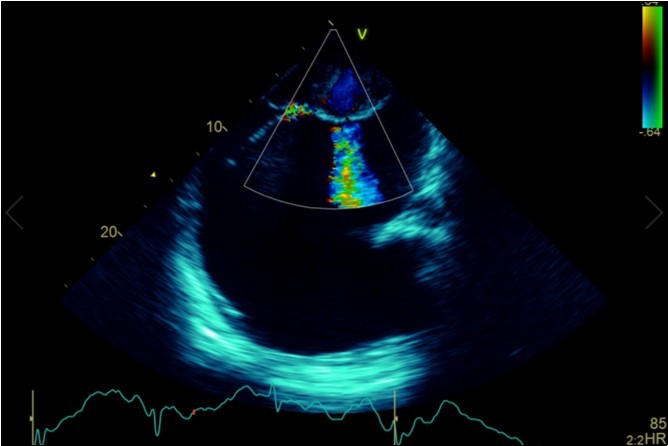

A dramatically dilated left atrium was seen on a TTE (see Figure 2a, Figure 2b, Figure 2c, and Figure 2d). Severe mitral stenosis with associated regurgitation was evident, with a mean gradient across the valve of 11mmHg and a hyperdynamic left ventricle. The left atrial volume measured by Simpson’s biplane method (see Figure 2c) was 2108mL, or 1548.5 ml/m2, based on height 1.55 metres and weight 44 Kg. Normal left atrial volume in a woman is 16 - 34 ml/m21. The computed tomography scan (CT) chest AP view (see Figure 3) is also shown.

Figure 2a.Transthoracic echocardiogram Apical 4C view. Findings include severely enlarged left atrium, severe mitral stenosis with associated regurgitation, a mean gradient across the valve of 11mmHg with a hyperdynamic left ventricle

Figure 2b.Transthoracic echocardiogram Parasternal long axis view. Findings include severe mitral stenosis (‘hockey-stick’ appearance to mitral valves), raised left atrial pressure (interatrial septum fixed and bowed to right)